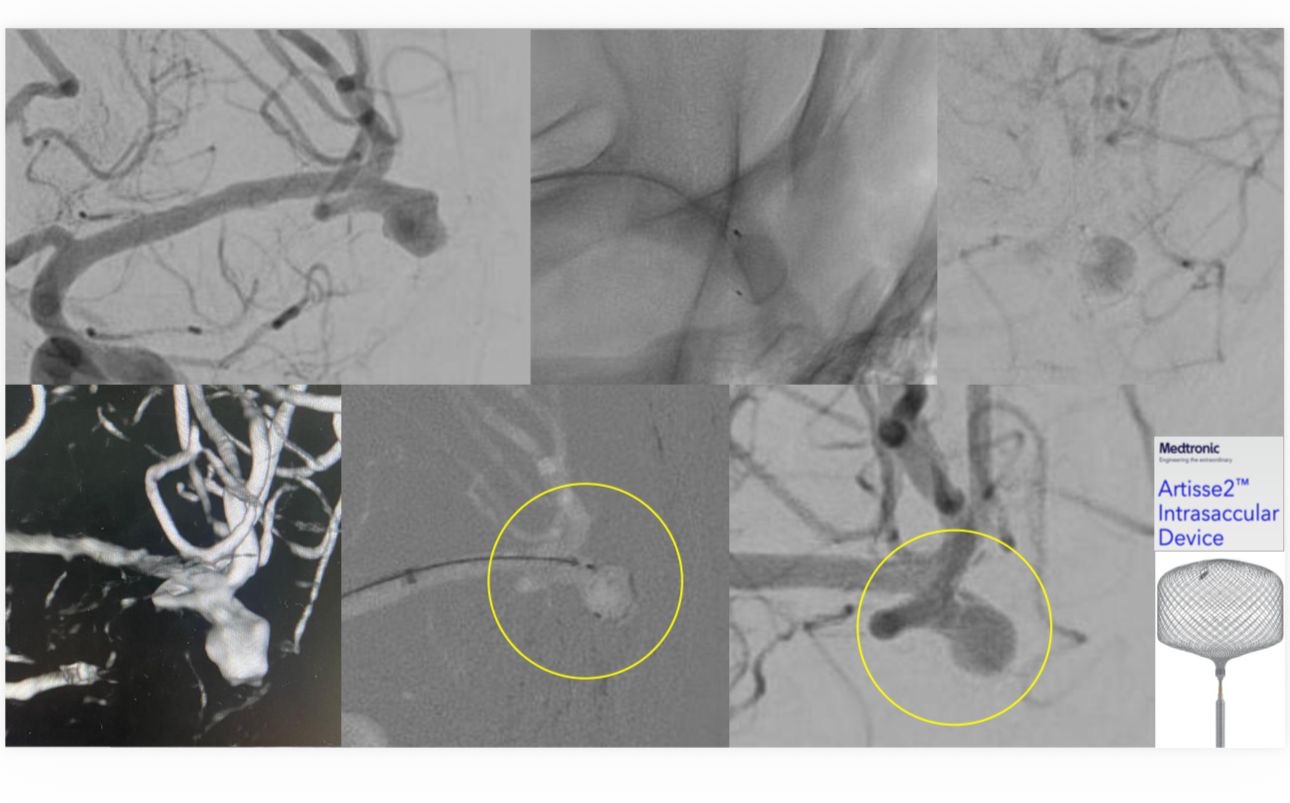

في أول استخدام سريري لتقنية Artisse™️ لعلاج تمدد شرياني دماغي واسع العنق بالمنطقة الشرقية

نجح فريق الأشعة العصبية التداخلية في مستشفى الملك فهد الجامعي التابع للمدينة الطبية الأكاديمية بجامعة الإمام عبدالرحمن بن فيصل، في علاج مريض يعاني من تمدد شرياني دماغي واسع العنق، وذلك في أول استخدام سريري لتقنية Artisse™️ في المنطقة الشرقية.

وتمكّن الفريق الطبي من إغلاق التمدد الشرياني بالكامل باستخدام التقنية الحديثة، وخرج المريض من المستشفى وهو بكامل عافيته ، حيث تتميز تقنية Artisse™️ بإمكانية زرع الجهاز داخل التمدد الشرياني بحيث يأخذ شكله بدقة، ما يسهم في تقليل زمن الإجراء وتقليل جرعة الأشعة والصبغة المستخدمة أثناء القسطرة، كما تتيح في كثير من الحالات تجنب استخدام مسيلات الدم بعد الإجراء، الأمر الذي يساعد في تسريع تعافي المريض وعودته إلى حياته اليومية بشكل أسرع.